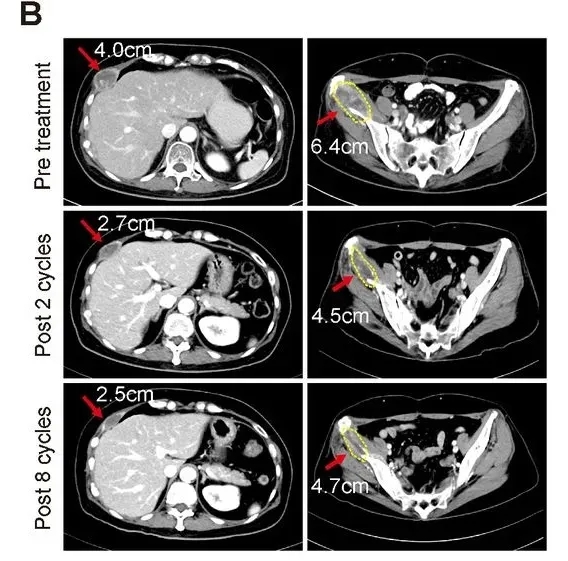

值得一提的是,其中1例55岁的转移性激素受体阳性、HER2阳性乳腺癌患者实现了部分缓解(PR):该患者既往已接受过抗HER2治疗、激素疗法及多种化疗,经连续2个周期联合治疗后达PR,并在第8周期治疗后仍维持这一状态(详见下图)。此外,其肿瘤标志物CA-153水平从治疗前的146.8,下降至治疗第5周期的75.4,治疗结束时仍稳定在76.6。

▲图源“AACR”,版权归原作者所有,如无意中侵犯了知识产权,请联系我们删除